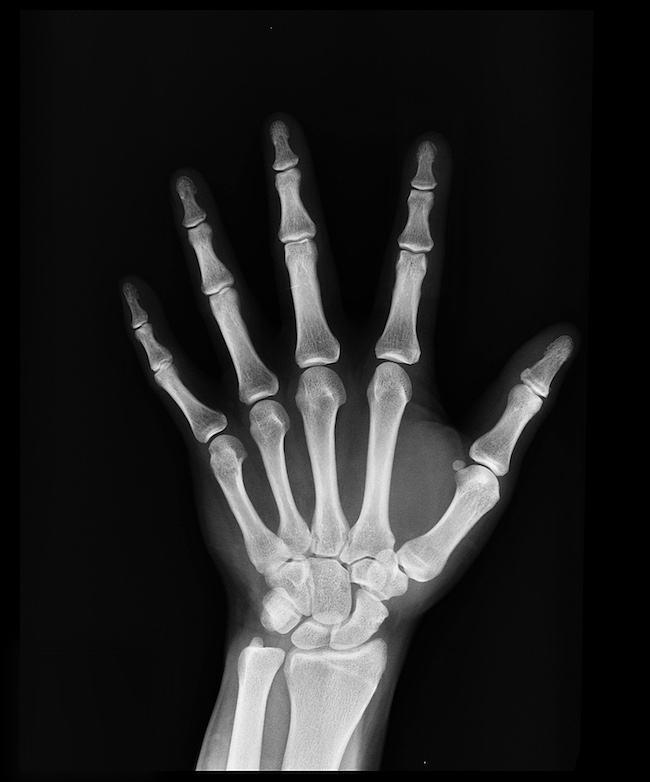

Knochen- und Skelettannotationen

Knochenkonturen und Struktursegmentierung

Wir kennzeichnen Knochenkonturen, Gelenkbereiche, Frakturbereiche und orthopädische Orientierungspunkte auf Skelett-Röntgenbildern.